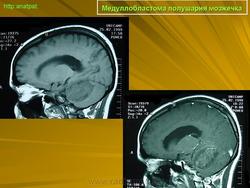

Медуллобластома - это опухоль, которая возникает из примитивных и эмбриональных клеток ЦНС. Локализируется исключительно в мозжечке и представляет 15-20% от детских опухолей мозга. 20% медуллобластом появляется в зрелом возрасте.

Это быстро растущая опухоль, очень злокачественна, имеющая тенденцию распространяться вдоль путей движения ликвора.

Вследствие локализации в мозжечке, обструкция путей циркуляции ликвора является достаточно частой и ранней, с последующей гидроцефалией. Синдром повышенного внутричерепного давления наряду с расстройствами равновесия, являются наиболее частыми и ранними признаками и симптомами.

Хирургическое лечение состоит в «радикальном» удалении опухоли, с последующей лучевой и химиотерапией, на которые медуллобластома часто очень чувствительна.